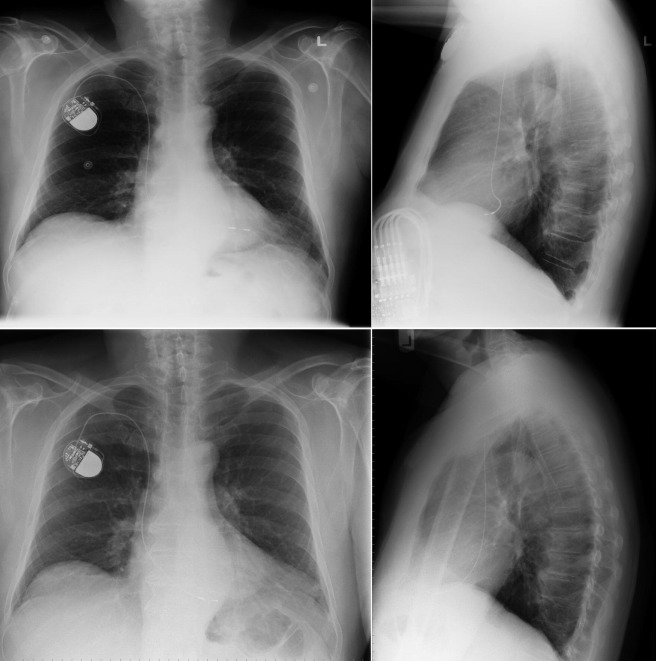

Chest radiography has a standard role in the identification of several potential complications such as pneumothorax, hemothorax, and several forms of malposition after insertion of pacemakers, implantable cardioverter defibrillators (ICDs), and cardiac resynchronization therapy devices.

Pacemaker leads are apparent, and ICDs are more obvious because of their larger coils. Coronary sinus leads for cardiac resynchronization therapy are finer leads.

Endocardial Pacer Leads

The position and integrity of endocardial pacer leads should be verified, especially when pacemaker dysfunction is clinically suspected ( Graphics 23-1 to 23-4 ; Figs. 23-1 to 23-15 ).The most common cause of pacemaker dysfunction that is apparent on the chest radiography is distal lead displacement/misplacement.

With a right atrial lead , the tip should be in the right atrial appendage.

With a right ventricular lead , the tip should lie anteriorly at the apex of the heart.